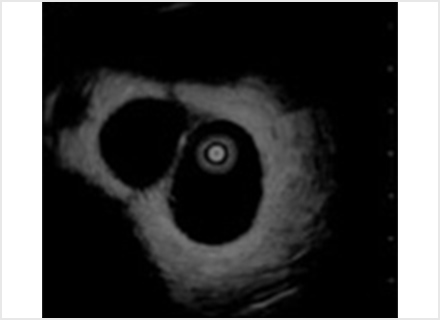

超音波内視鏡検査:EUS(Endoscopic Ultrasonography)

超音波内視鏡検査は、内視鏡装置(胃カメラ)の先端部分に超音波(エコー)を発生する器械が装着されており、消化管や周辺臓器の断面像を描出する検査です。 体外式超音波検査とは異なり、胃や腸の中の空気や脂肪が、画像化の妨げになることはありません。 超音波内視鏡検査はより詳細な画像情報が取得でき、病巣がどのくらいまで深く進展しているか、リンパ節転移や、周りの臓器への浸潤(しんじゅん)などについての詳細な情報を得ることができます。さらに、胃や十二指腸と隣接している胆嚢・胆管 ・膵臓なども、胃壁あるいは十二指腸を通して精密に調べることができます。 このような精密な画像検査は、手術における切除範囲の決定等、治療方針に重要な役割を果たします。 精密検査になりますので検査時間は通常の内視鏡検査と比べ長くなります。

超音波内視鏡下穿刺吸引法:EUS- FNA(Fine needle aspiration)

超音波内視鏡下穿刺吸引法(EUS-FNA)は、胃や十二指腸の消化管から(超音波内視鏡:EUS)で膵臓・胆道などの腫瘤を観察し、消化管内から針を刺して組織を採取する方法です。 直接組織を採取し評価することにより、診断や治療方針の決定に役立ちます。

管腔内超音波検査:IDUS(intraductal ultrasonography)

管腔内超音波検査(IDSU)は内視鏡の鉗子口から胆管や膵管に細長い管状の超音波を挿入し超音波画像を得る検査です。 細い胆管や膵管は腹部超音波検査や超音波内視鏡検査でも観察困難な場所ですが、内視鏡的逆行性膵胆管造影(ERCP)検査で細い超音波プローブを直接胆管や膵管に挿入することでより、詳細な画像情報を得ることが可能です。